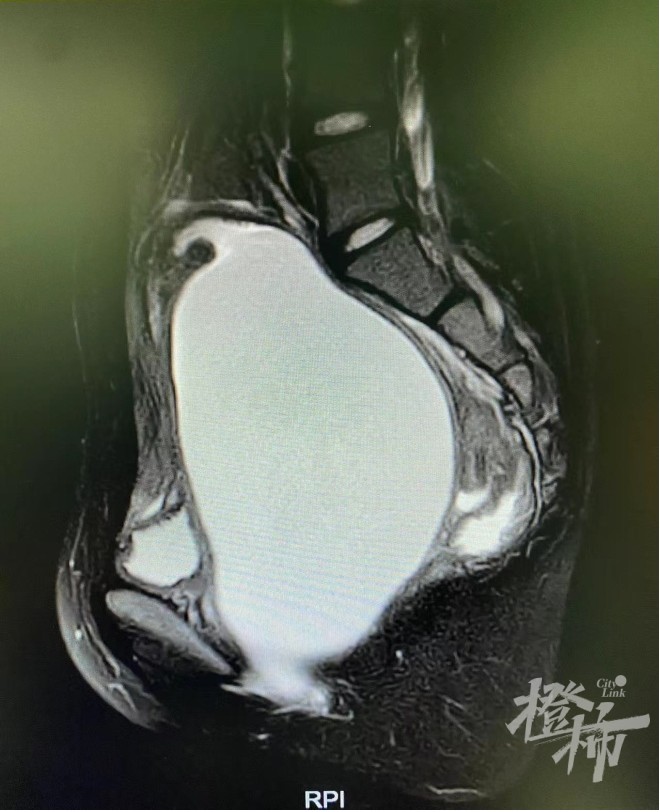

术前的盆腔MR:可看到一个巨大包块

不承想,5天前,言言突然喊肚子痛,严重时小便都不顺畅。临近期末,为了不影响复习,C女士和言言想熬一熬过了期末再说。忍了3天,言言的腹痛一直没有消失,周日C女士便带她去附近的社区医院检查,B超提示盆腔内见13.3cm×9.5cm肿块,比胎头还大,社区医院没法处理,建议到上级医院就诊。